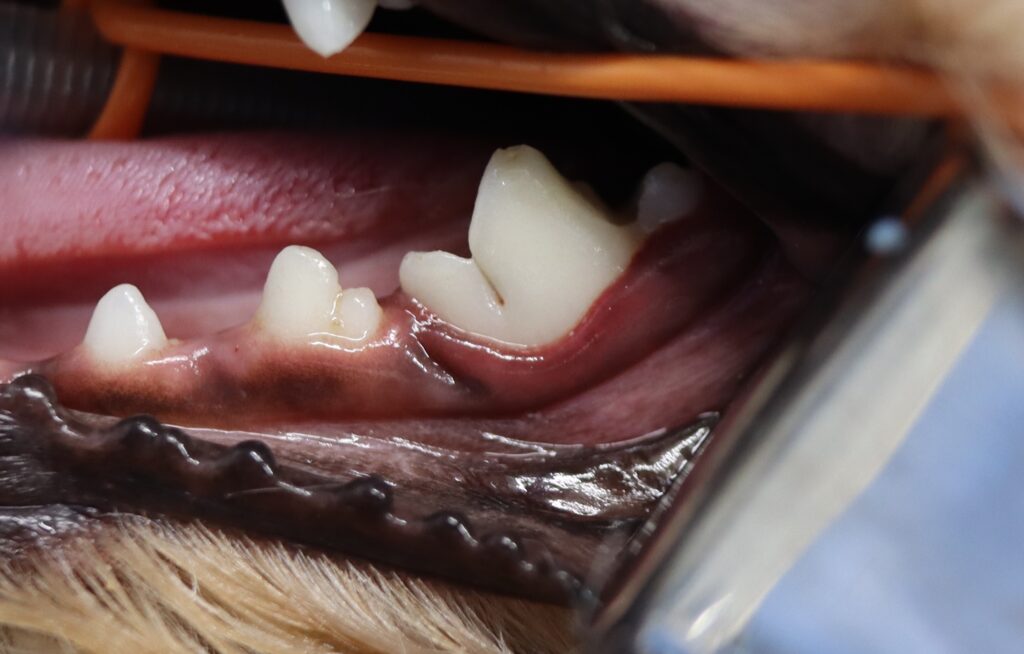

症例紹介:2歳トイプードル

今回の症例は、2歳のトイプードルです。

- 左下顎第一後臼歯に歯石を認める

- 歯肉が浮腫状に腫れ、赤みが強い